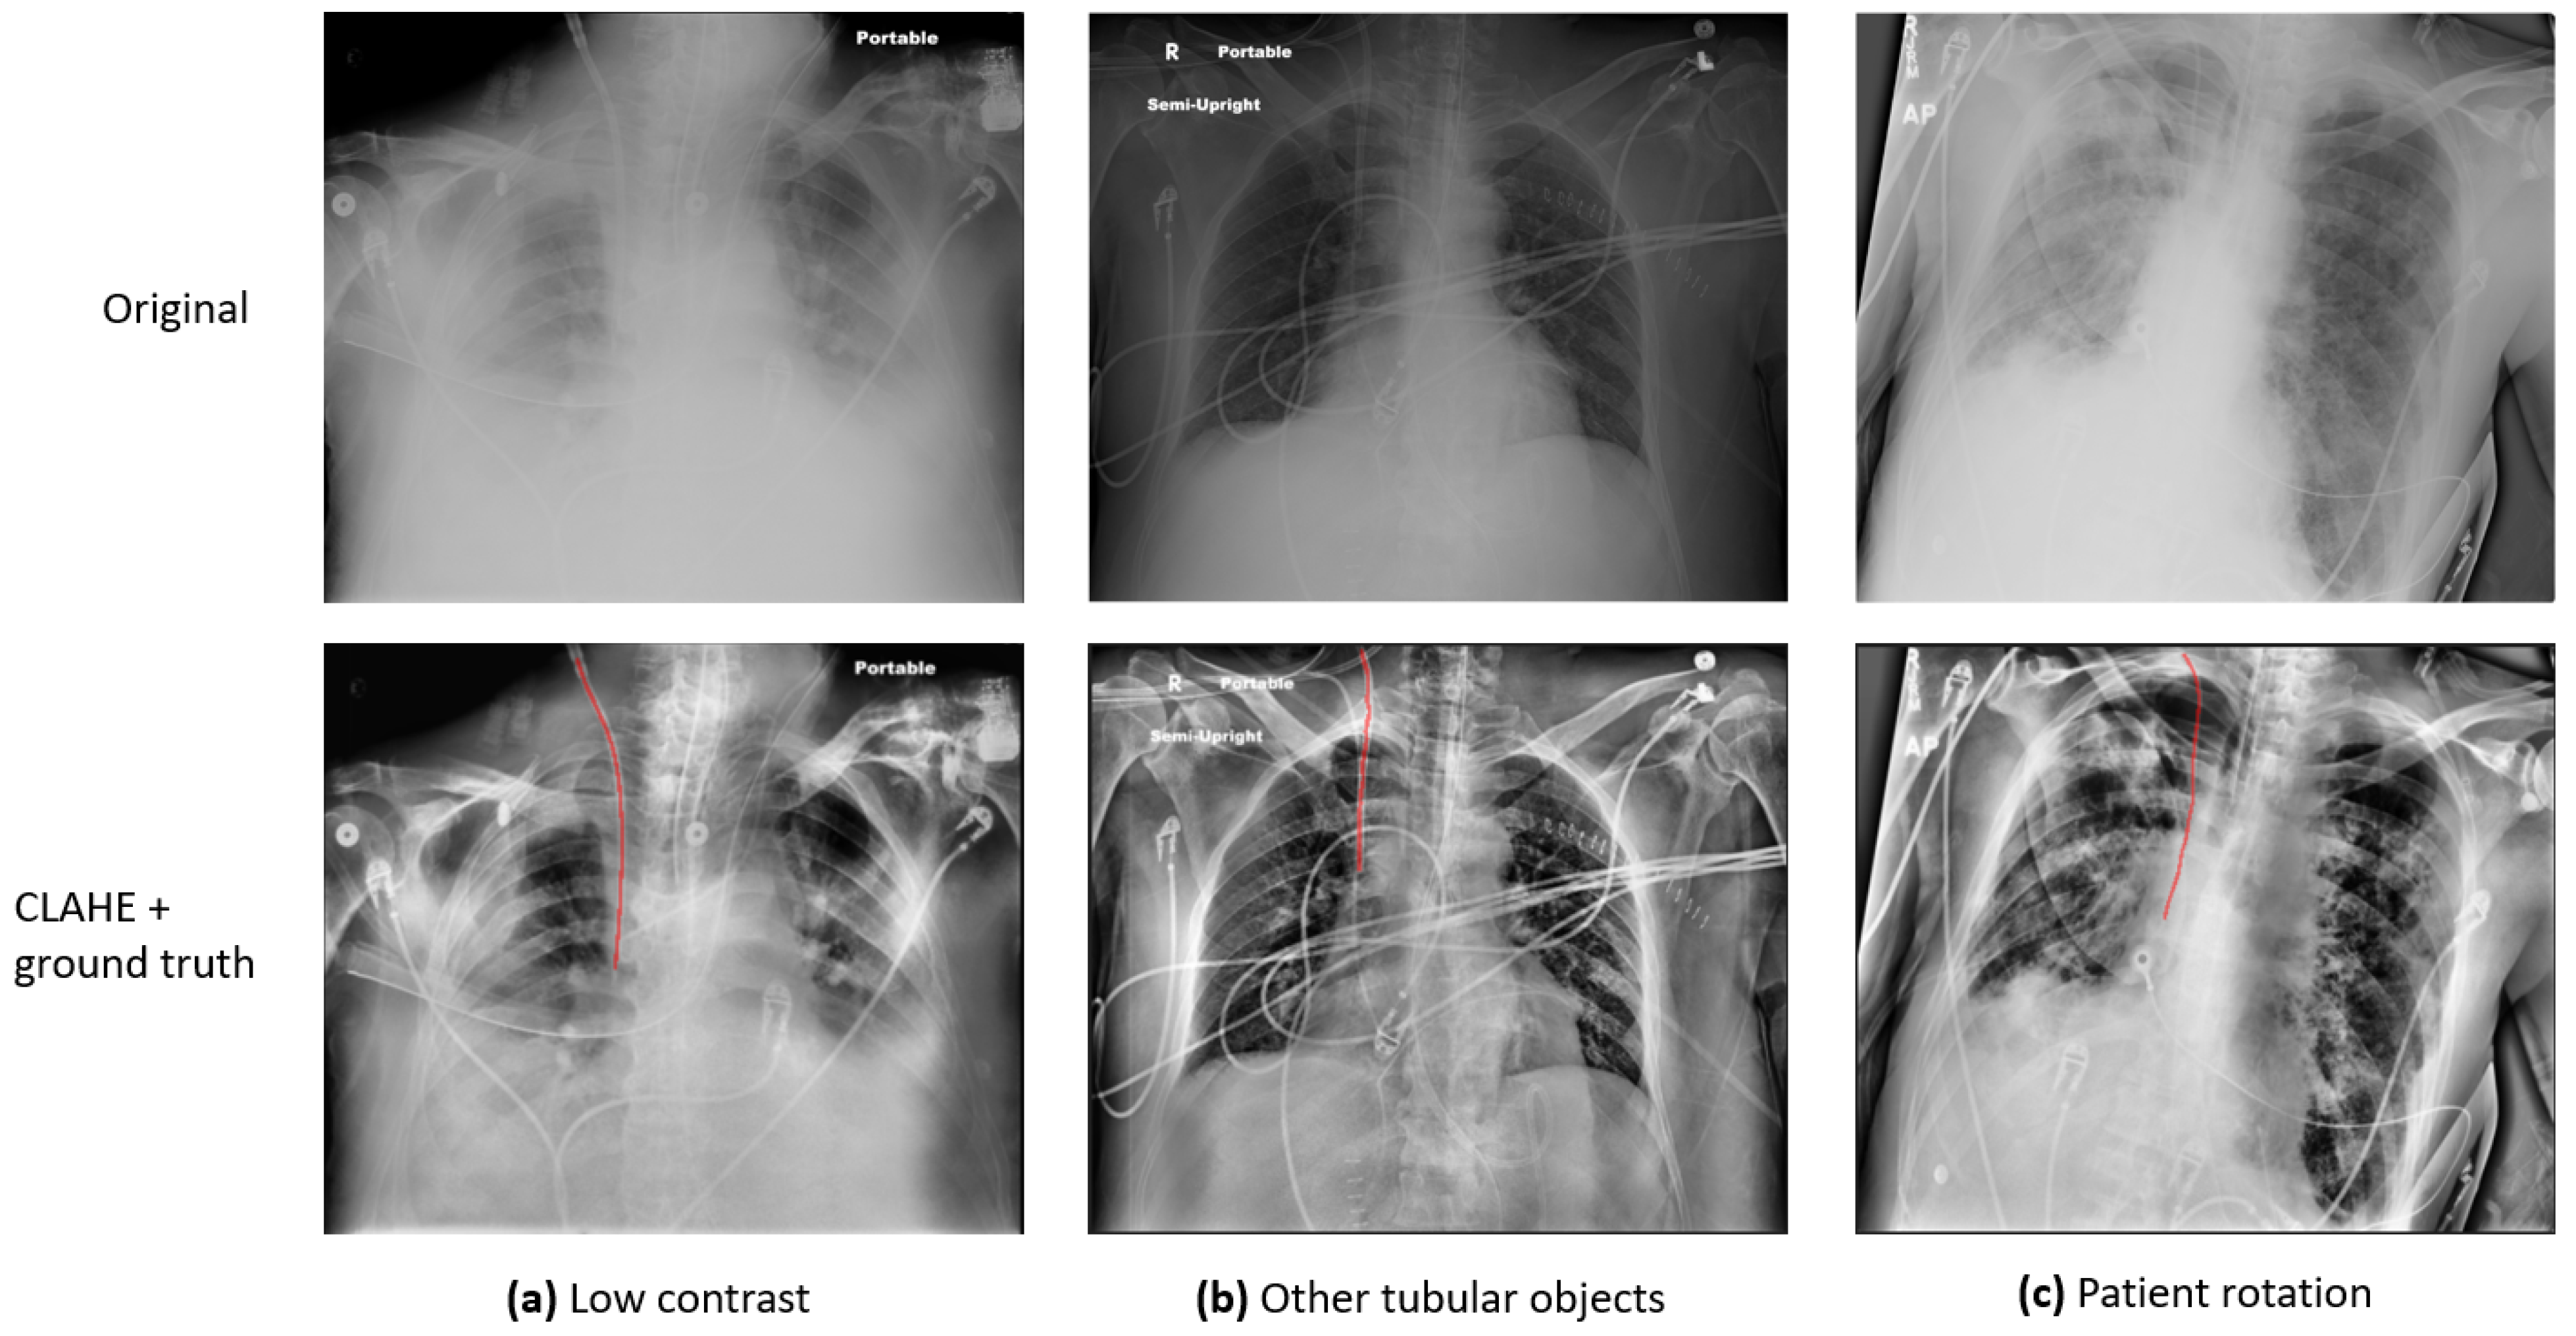

Previous studies [4,5] have identified several major challenges in the automatic detection and evaluation of CVCs in CXR images: (1) Some CXRs are of low pixel contrast. (2) The CVC is a narrow, tubular structure that occupies a disproportionately small area of the full CXR image, which makes it challenging to detect. (3) In addition to the CVC, other tubes and anatomical structures with similar appearances may also be present in a single CXR, and they can be difficult to distinguish. (4) Since the CXRs are acquired on ICU patients, the images might be rotated, adding another degree of variation to the image quality. Figure 1 presents a few sample images demonstrating these variations: (a) presents an image of low contrast and preprocessing is required to enhance the visibility of anatomy and foreign objects; (b) exhibits an image in which there are multiple tubular objects, which can be indistinguishable from one another; (c) shows a rotated patient, which can significantly affect clinical decisions. To address the challenges, various investigations have been conducted, and a detailed review is provided in Section 2: Literature Review.

Figure 1. Sample CXR images to demonstrate the variation of image quality. The first row presents the original images. The second row presents the processed ones with CLAHE overlaid with the ground truth label, marked with red lines.